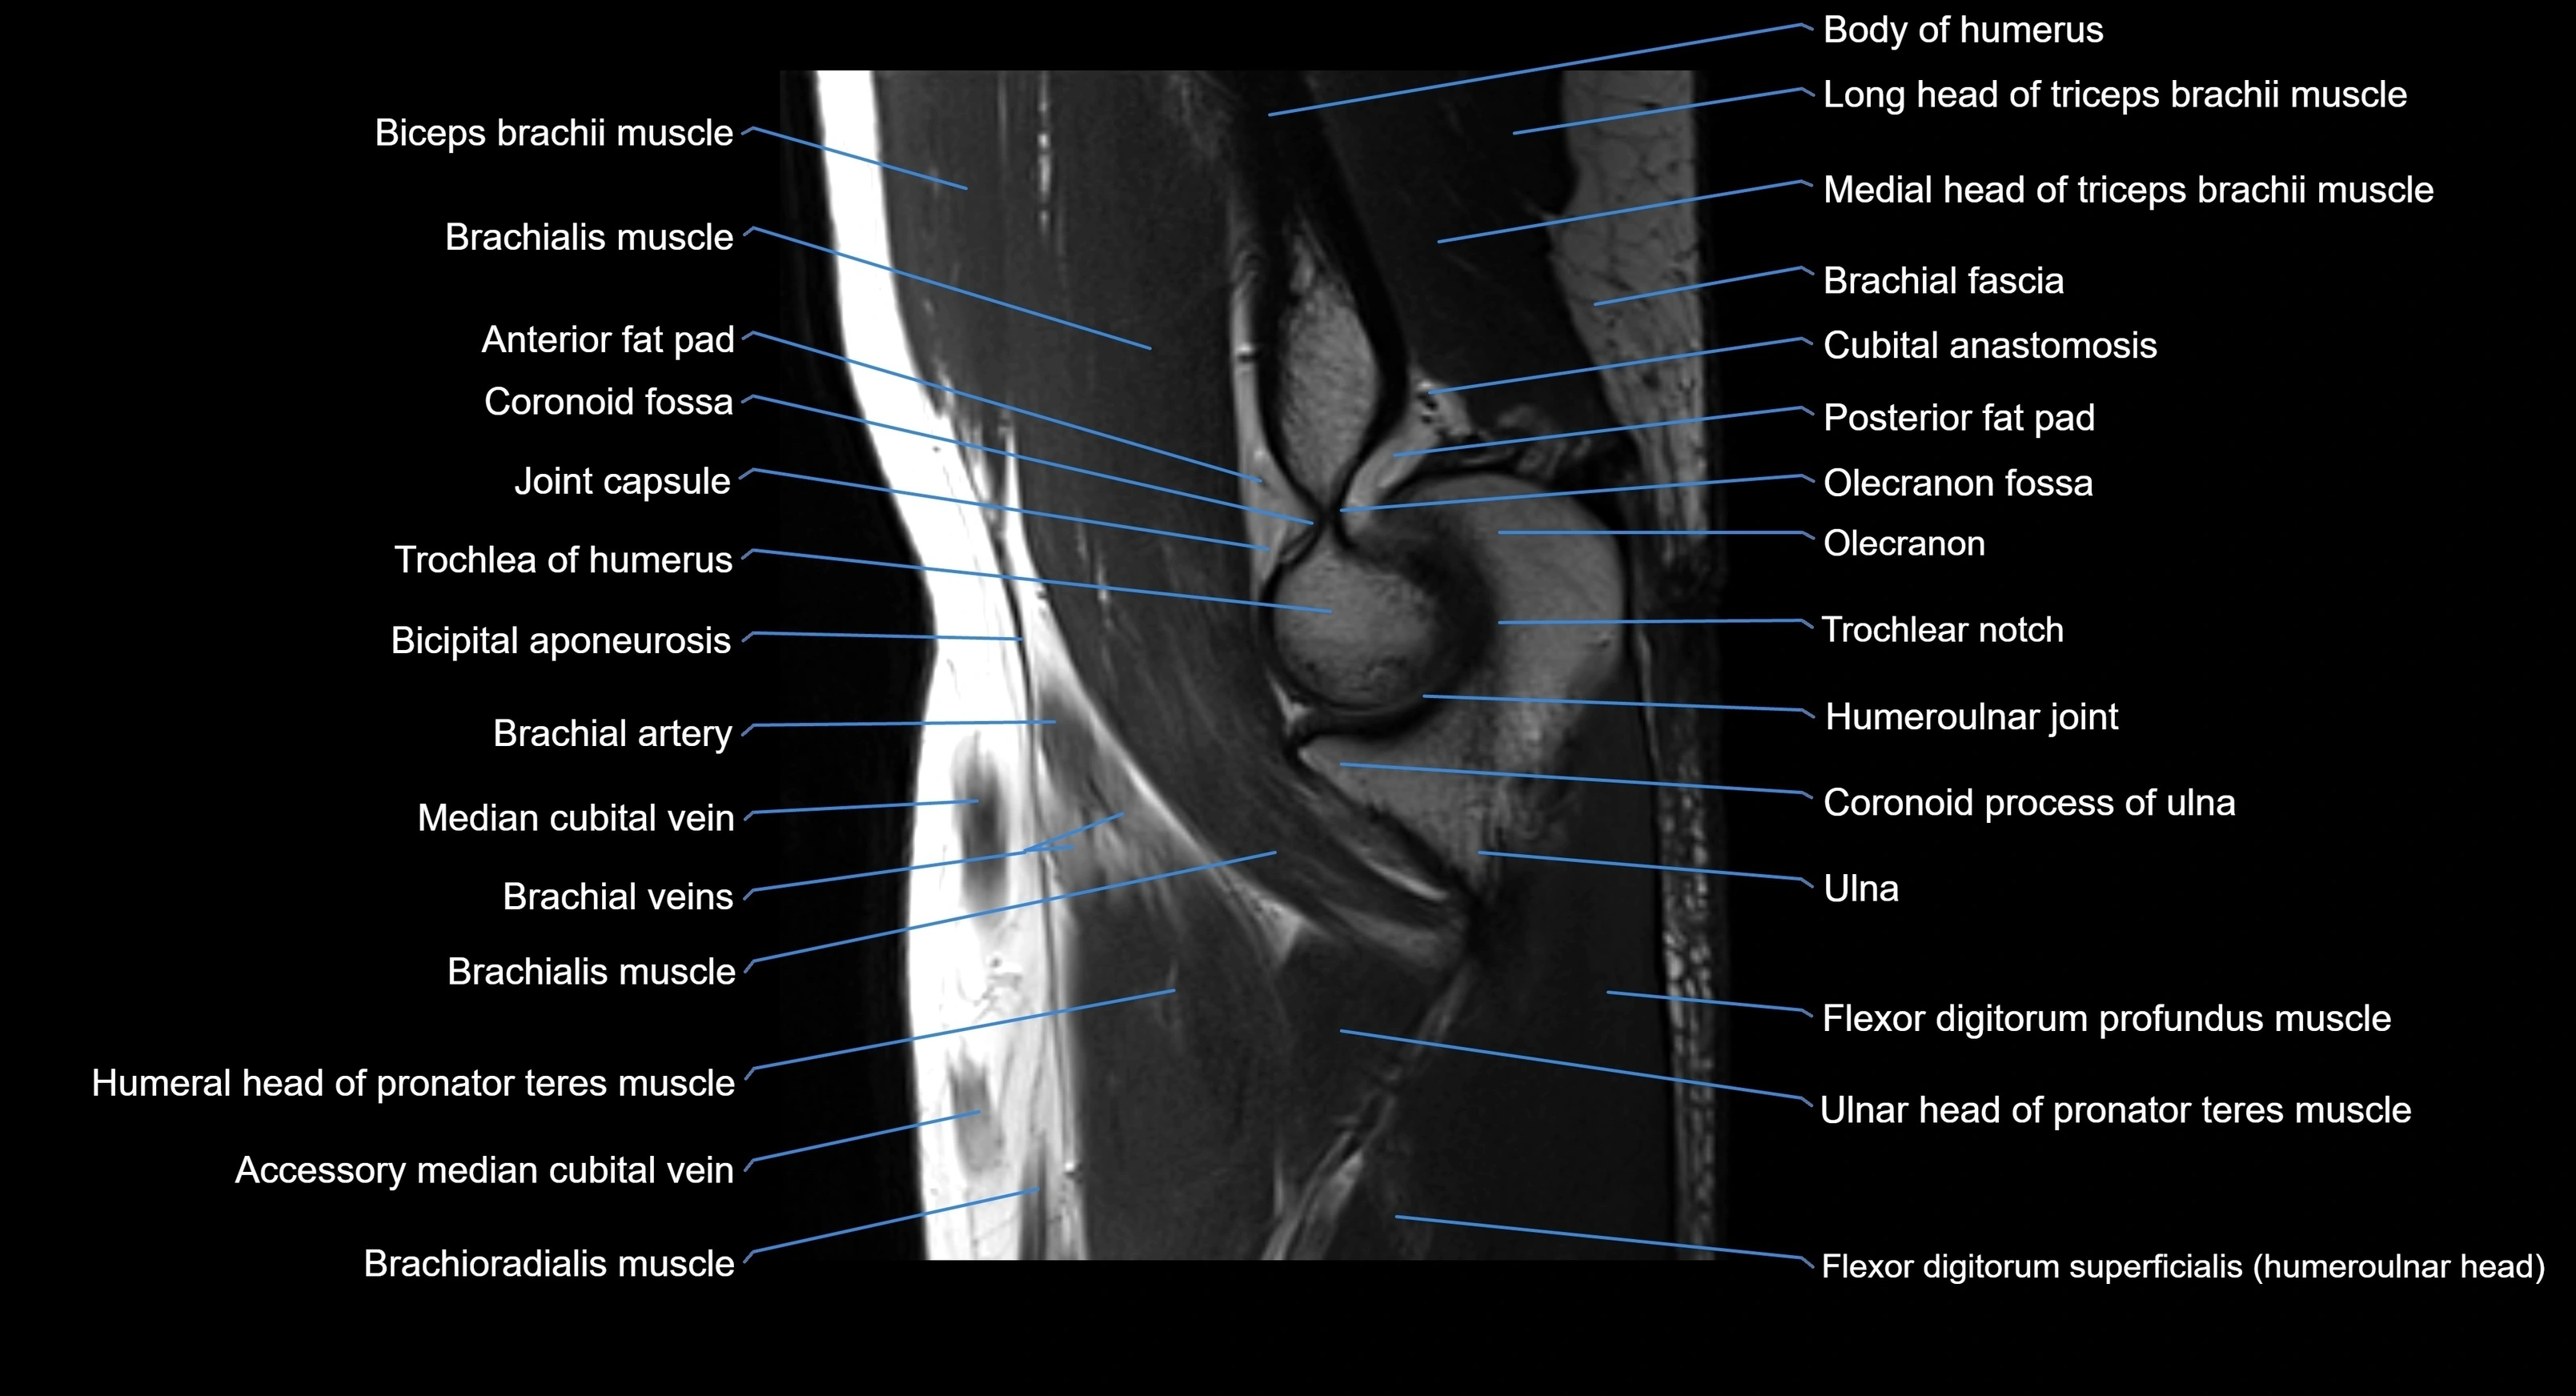

MRI image

image